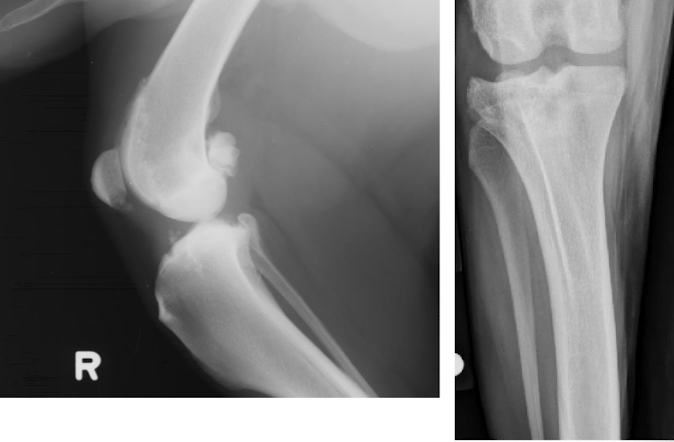

What is the arrow pointing to?

large osteophyte on the anconeal process (earliest change seen in DJD)

osteophyte on the medial coronoid process in elbow DJD

What are 4 common osteophyte locations for stifle DJD?

apex of the patella

trochlear groove

medial and lateral aspects of the distal femur and proximal tibia

fabellae